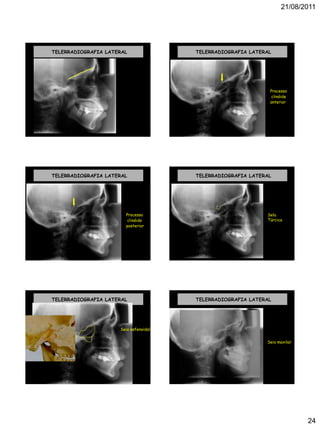

TELERRADIOGRAFIA LATERAL TELERRADIOGRAFIA LATERAL

Processo

clinóide

anterior

TELERRADIOGRAFIA LATERAL

posterior

Sela

Túrcica

Seio esfenoidal

Seio maxilar